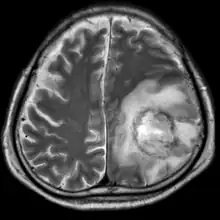

T2-weighted MRI showing a necrotic brain absess as a result of GAE caused by an infection of Acanthamoeba, genotype T18